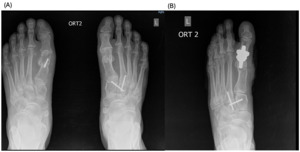

The patients had undergone radiographic evaluation of the MTP joint before the surgery, right after surgery, and 2 and 6 months after surgery (Figures 4-9). The radiographic imaging after the surgery confirmed the correct positioning and alignment. At the follow-up, the radiographic images were done to analyze the early healing process, to observe if there were any signs of implant loosening. 2 months after the surgery, no patient had periprosthetic radiolucencies, no stress-related changes. 6 months after surgery, no osteolysis, no migration of the implant.

This case series demonstrates successful short-term results following total first metatarsophalangeal (MTP) joint replacement using ceramic implants in patients with hallux rigidus. All three patients presented significant improvement in AOFAS scores within 2 months postoperatively, with preserved improvement at 6 months. Notably, Patient C, who had the lowest preoperative score (27/100), achieved the greatest relative improvement, reaching 92/100 at 2 months and 89/100 at 6 months. These functional outcomes were confirmed by physical examination findings, with clear improvements in joint alignment and reduction in deformity (Figure 1-3, (B, C)). Moreover, radiographic imaging revealed no signs of complications such as implant loosening, migration or stress-related changes.

._patient_a__immediate_postoperative_radiograph_(b).png)

._patient_a__6-month_follow-up_radiograph_(b).png)

._patient_b__immediate_postoperative_radiograph_(b).png)

._patient_b__6-month_follow-up_radiograph_(b).png)

._patient_c__immediate_postoperative_radiograph_(b).png)

._patient_c__6-month_follow-up_radiograph_(b).png)